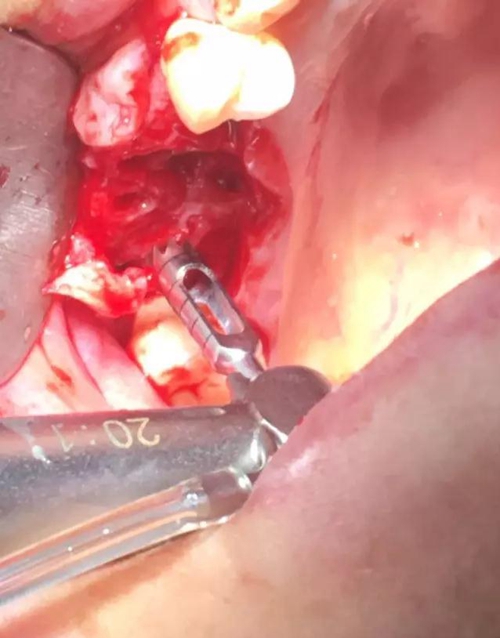

【病例分享】內(nèi)提,用自體骨柱,不用骨粉

2.jpg